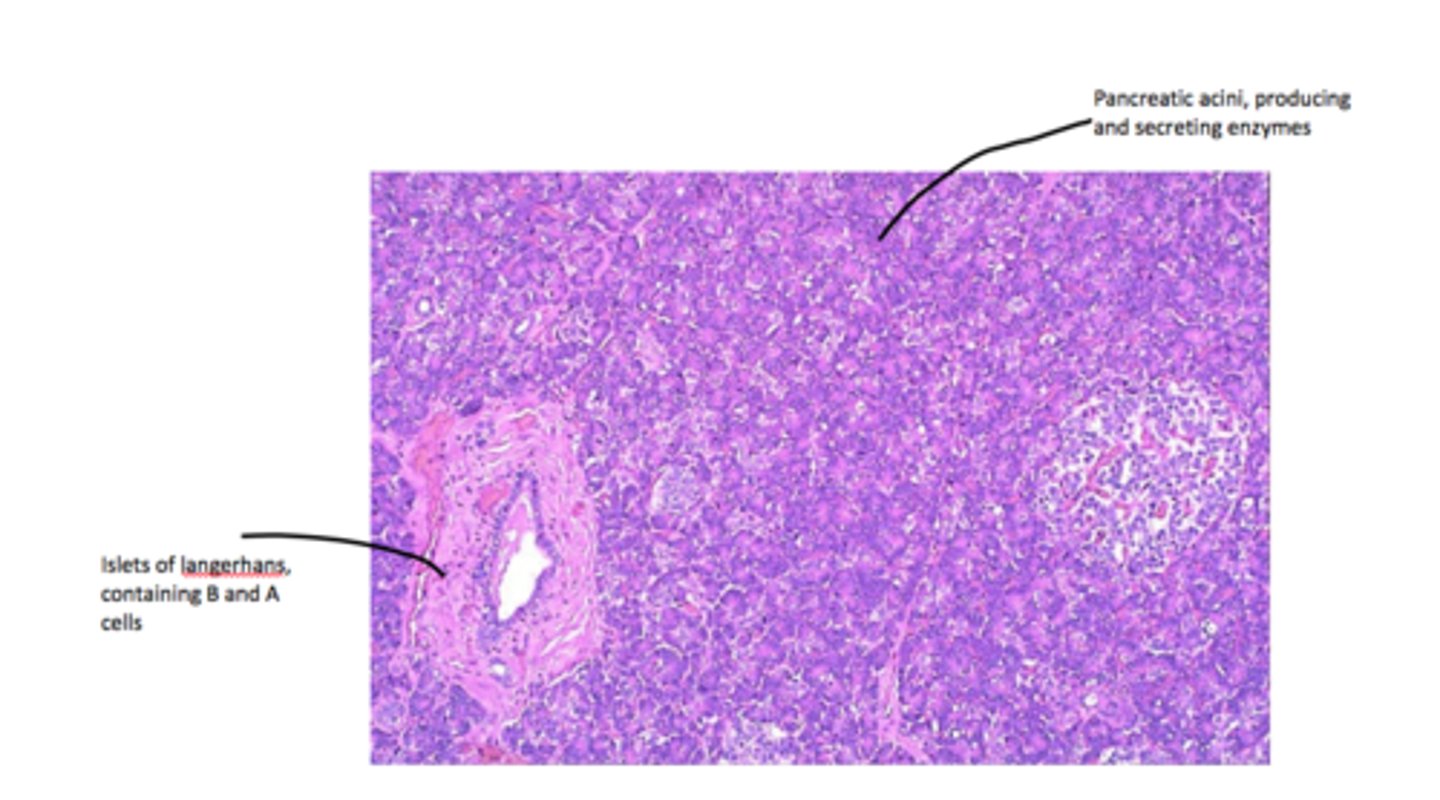

pancreas

label each part